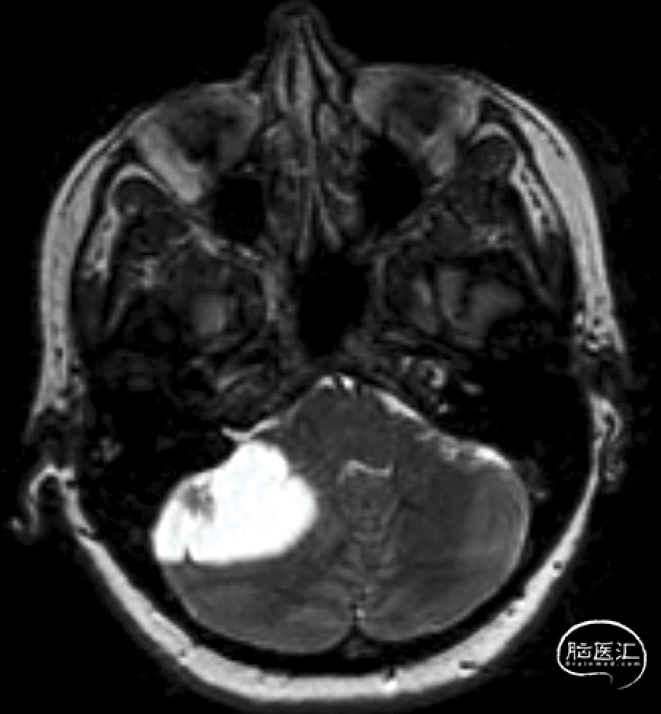

一名 11 岁男孩出现头痛和视力模糊。 (A) 术前 MRI 扫描显示6.1 ×4.0× 3.4cm T2 高信号和对比增强。(B)部分切除后的术后 MRI扫描,肿瘤位于视路中。组织学证实了 BRAFV600E 突变的毛细胞星形细胞瘤。 (C) MEK 抑制剂治疗 4周后的后续 MRI 扫描显示肿瘤几乎完全消退。

Children 2021, 8(11), 1075;https://doi.org/10.3390/children8111075